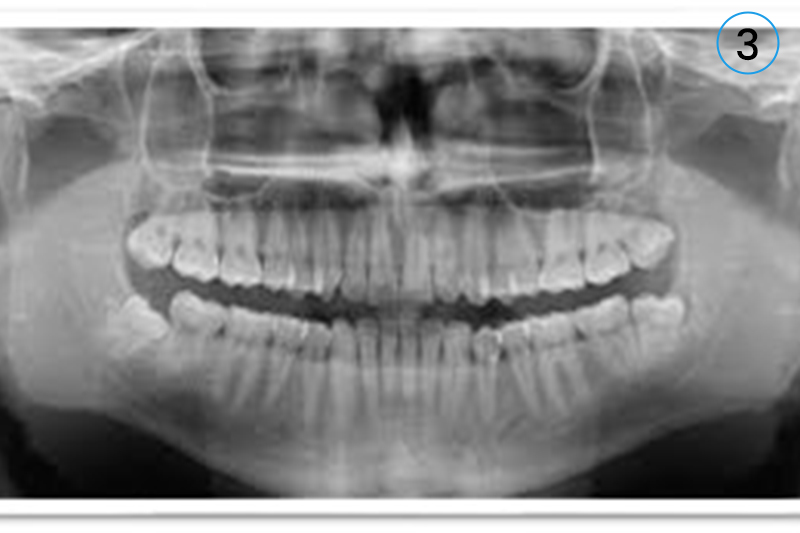

• 3. OPG (Digital Format)